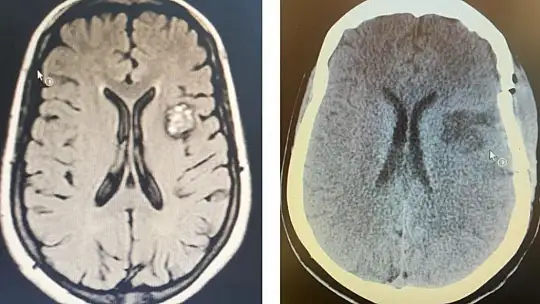

Balıkesir Üniversitesi Hastanesi, Balıkesir ve çevresine sunduğu nitelikli sağlık hizmetleri ile bölgede sağlık alanında önemli bir merkez olarak faaliyetlerini sürdürüyor. Hastanede farklı birimler bünyesinde gerçekleştirilen, “Balıkesir’de ilk” niteliği taşıyan işlemlere bir yenisi de Beyin ve Sinir Cerrahisi Anabilim Dalı öğretim üyelerince eklendi. MR incelemesinde beynin sol tarafında “kavernom” adı verilen beyin damar yumakçığı tespit edilen hasta, Doç. Dr. Utku Adilay ve Dr. Öğr. Üyesi Salim Katar tarafından ameliyat edildi.

Gerçekleştirilen ameliyatla ilgili bilgiler veren Beyin ve Sinir Cerrahisi Anabilim Dalı Başkanı Doç. Dr. Utku Adilay, boyun, baş ve çenede kasılmalar ile karakterize sara nöbeti şikâyetiyle başvurduğu hastaneden, üniversite hastanesine yönlendirilen 49 yaşındaki yabancı uyruklu hastanın beyin MR incelemesinde, beyninin sol tarafında kavernom adı verilen beyin damar yumakçığı tespit edildiğini belirterek, ameliyatının da klinik bünyesinde nöronavigasyon sistemi ile başarıyla gerçekleştirildiğini belirtti. Adilay, yapılan ameliyatın üniversite hastanesi ve Balıkesir için bir ilk olma niteliği taşıdığını sözlerine ekledi.

Gerçekleştirdikleri operasyonun detaylarını anlatan Beyin ve Sinir Cerrahisi Anabilim Dalından Dr. Öğr. Üyesi Salim Katar da “Genellikle beyinde, nadiren de omurilikte yerleşen damarsal bir bozukluk olan kavernom ya da kavernöz hemanjiom dediğimiz lezyonlar, beyin kanamasına ve epileptik nöbetlere neden olabilirler. Hastamızda olduğu gibi ilaçlarla engellenemeyen nöbetler varsa veya ilaçların yan etkileri rahatsız edici derecede ise cerrahi işleme gerek duyulur. Genellikle önerilen tedavi yolu kraniotomi denilen ameliyat yöntemidir. Beyin ameliyatlarında en kritik noktalardan birisi, normal beyin dokusuna zarar vermeden en güvenli ve kısa yoldan beyin lezyonunu olabildiğince tama yakın çıkarabilmektir. Beynin derininde yerleşmiş tümör ve damar yumağı gibi lezyonların ameliyatında bu durum daha da önem kazanır. Hastamızda olduğu gibi derin yerleşimli kavernom gibi vakalarda önemli husus, damar yumağını beyne zarar vermeden en kısa ve güvenli yoldan bulmaktır. ‘Nöronavigasyon Sistemi’ beyinde hedeflediğimiz bir bölgeye hata payını en aza indirecek şekilde ulaşmamızı sağlayan ve son yıllarda kullanıma giren yüksek teknolojili, ameliyatlara yardımcı bir sistemdir. Bu tip durumlarda nöronavigasyon, ameliyat güvenliğini ve konforunu arttıran cerrahiye yardımcı bir yöntemdir. Üniversite hastanemizde gerekli olduğunu düşündüğümüz vakalarda, kritik alanlarda ve derin yerleşimli tümörlerde ve kavernomlarda, nöronavigasyon sistemini başarı ile kullanmaktayız. Sonuç olarak hastadaki kavernom, total olarak çıkarıldı. Şu an hastamızın genel durumu çok iyi, nöbetleri kesildi ve herhangi bir şikâyeti yok” şeklinde konuştu.